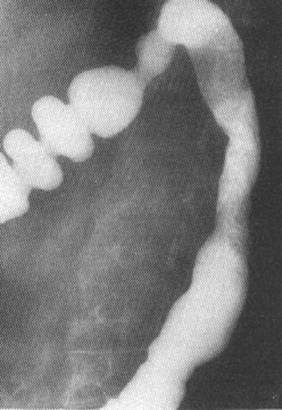

Fig. 50 – Colita ischemica (disparitia haustratiei si ingustare lunga, putin marcata a lumenului colic, interesand unghiul splenic)

5. Colita ischemica

Ischemia colonului este de obicei cronica determinand initial edem mucos si hemoragie, iar in stadiile tardive stenoza. Leziunile sunt localizate intre unghiul splenic si colonul sigmoid si constau in neregularitati de contur digitiforme si stenoze largi si extinse.